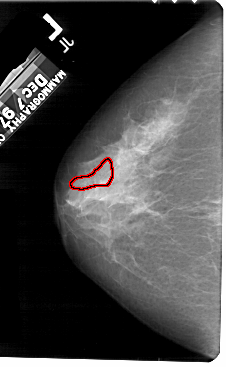

FILE: A_1584_1.LEFT_CC.OVERLAY

TOTAL_ABNORMALITIES 1

ABNORMALITY 1

LESION_TYPE CALCIFICATION TYPE PLEOMORPHIC DISTRIBUTION SEGMENTAL

ASSESSMENT 4

SUBTLETY 4

PATHOLOGY MALIGNANT

TOTAL_OUTLINES 1

BOUNDARY